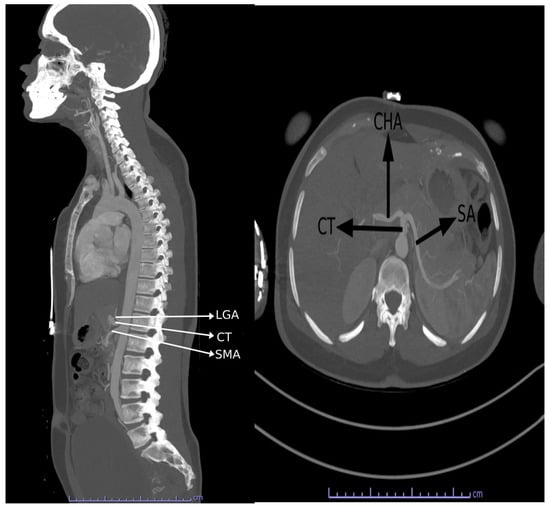

The CT normally trifurcates into the left gastric, splenic, and common hepatic arteries. Figure 5 shows the 3D construction of the normal branching of the CT. The CT showed classical trifurcation in 112 (96.60%) patients, where it divided into the splenic artery, left gastric artery, and the common hepatic artery. In the other four patients, bifurcation of the CT was observed. In two (1.70%) out of the four patients (one male and one female), the CT gave rise to the splenic and left gastric artery (gastrosplenic trunk; Uflacker’s type V), while the common hepatic artery took origin from the superior mesenteric artery. Figure 6 shows a common hepatic artery originating from the superior mesenteric artery. In the other two patients (1.70%) (one male and one female), the CT gave rise to the splenic and common hepatic artery (hepatosplenic trunk; Uflacker’s type II), while the left gastric artery arose as a direct branch from the abdominal aorta. Figure 7 shows the left gastric originating from the abdominal aorta, while the CT bifurcates into the SA and common hepatic artery.

Figure 5. Three-dimensional reconstructions demonstrating the normal trifurcation of the CT into the left gastric artery (LGA), splenic artery (SA), and common hepatic artery (CHA).